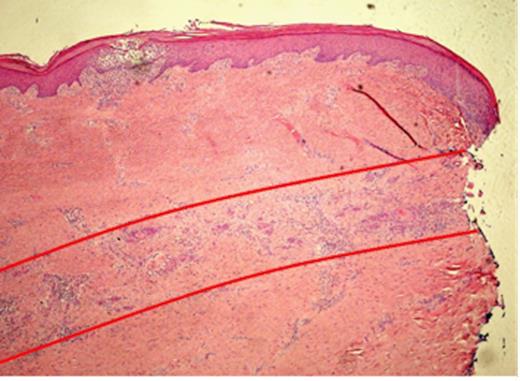

Pathological examination of the plantar fascia revealed extensive invasion of the subcutis, extending radially for up to 15mm beyond the area of ulceration (Fig. 1). The tumour was 6mm thick and confined to the subcutaneous plane, well clear of the underlying muscle and bone. Microscopic examination of indurated areas revealed a moderately differentiated SCC invading the deep dermis in a band-like fashion parallel to the epidermis without evidence of peri-neural or deep structure involvement (Fig. 3).

Histopathological slide of the indurated skin taken 10mm away from the ulcer showing a moderately differentiated Squamous Cell Carcinoma invading the deep dermis in a band like fashion, parallel to the epidermis (red lines). The local infiltration is well confined to the subcutaneous plane without peri-neural or deep structure involvement